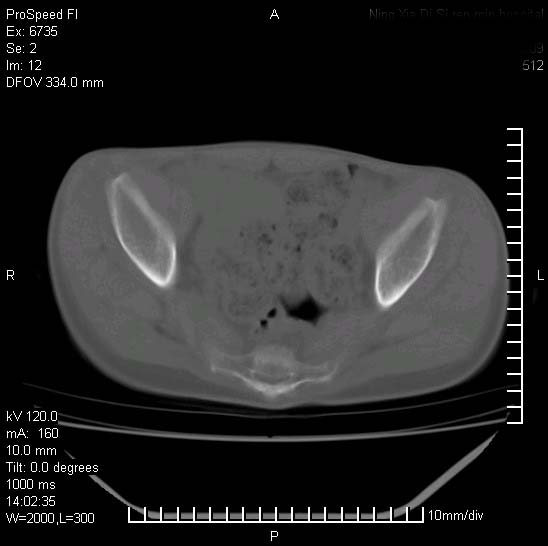

患者自诉胯部疼痛两年余,在当地服用中药,半月前至本院考虑骶髂关节结核,给予抗痨治疗。现发展至右下肢疼痛明显,活动受限,以膝关节处明显,拍膝关节平片无明显异常。

两侧骶骼关节改变,考虑强直性脊炎

左侧骶髂关节面限局性骨破坏,边缘硬化关节腔见钙化物;不出外tb

右侧骶髂关节也有类似改变,只是较左侧轻,首先考虑强直性脊柱炎,不除外结核,建议作hla-b27检查。

典型强脊炎改变,髋关节亦有累及

符合强直性脊柱炎表现。